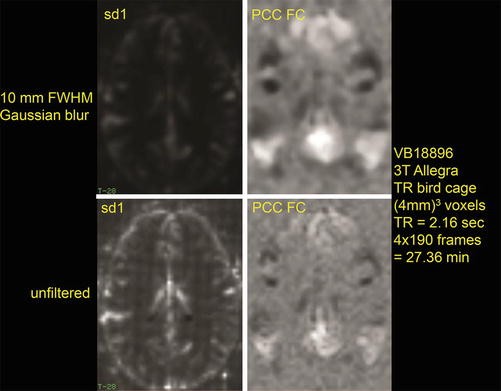

Intrinsic Brain Activity And Resting State Networks Springerlink